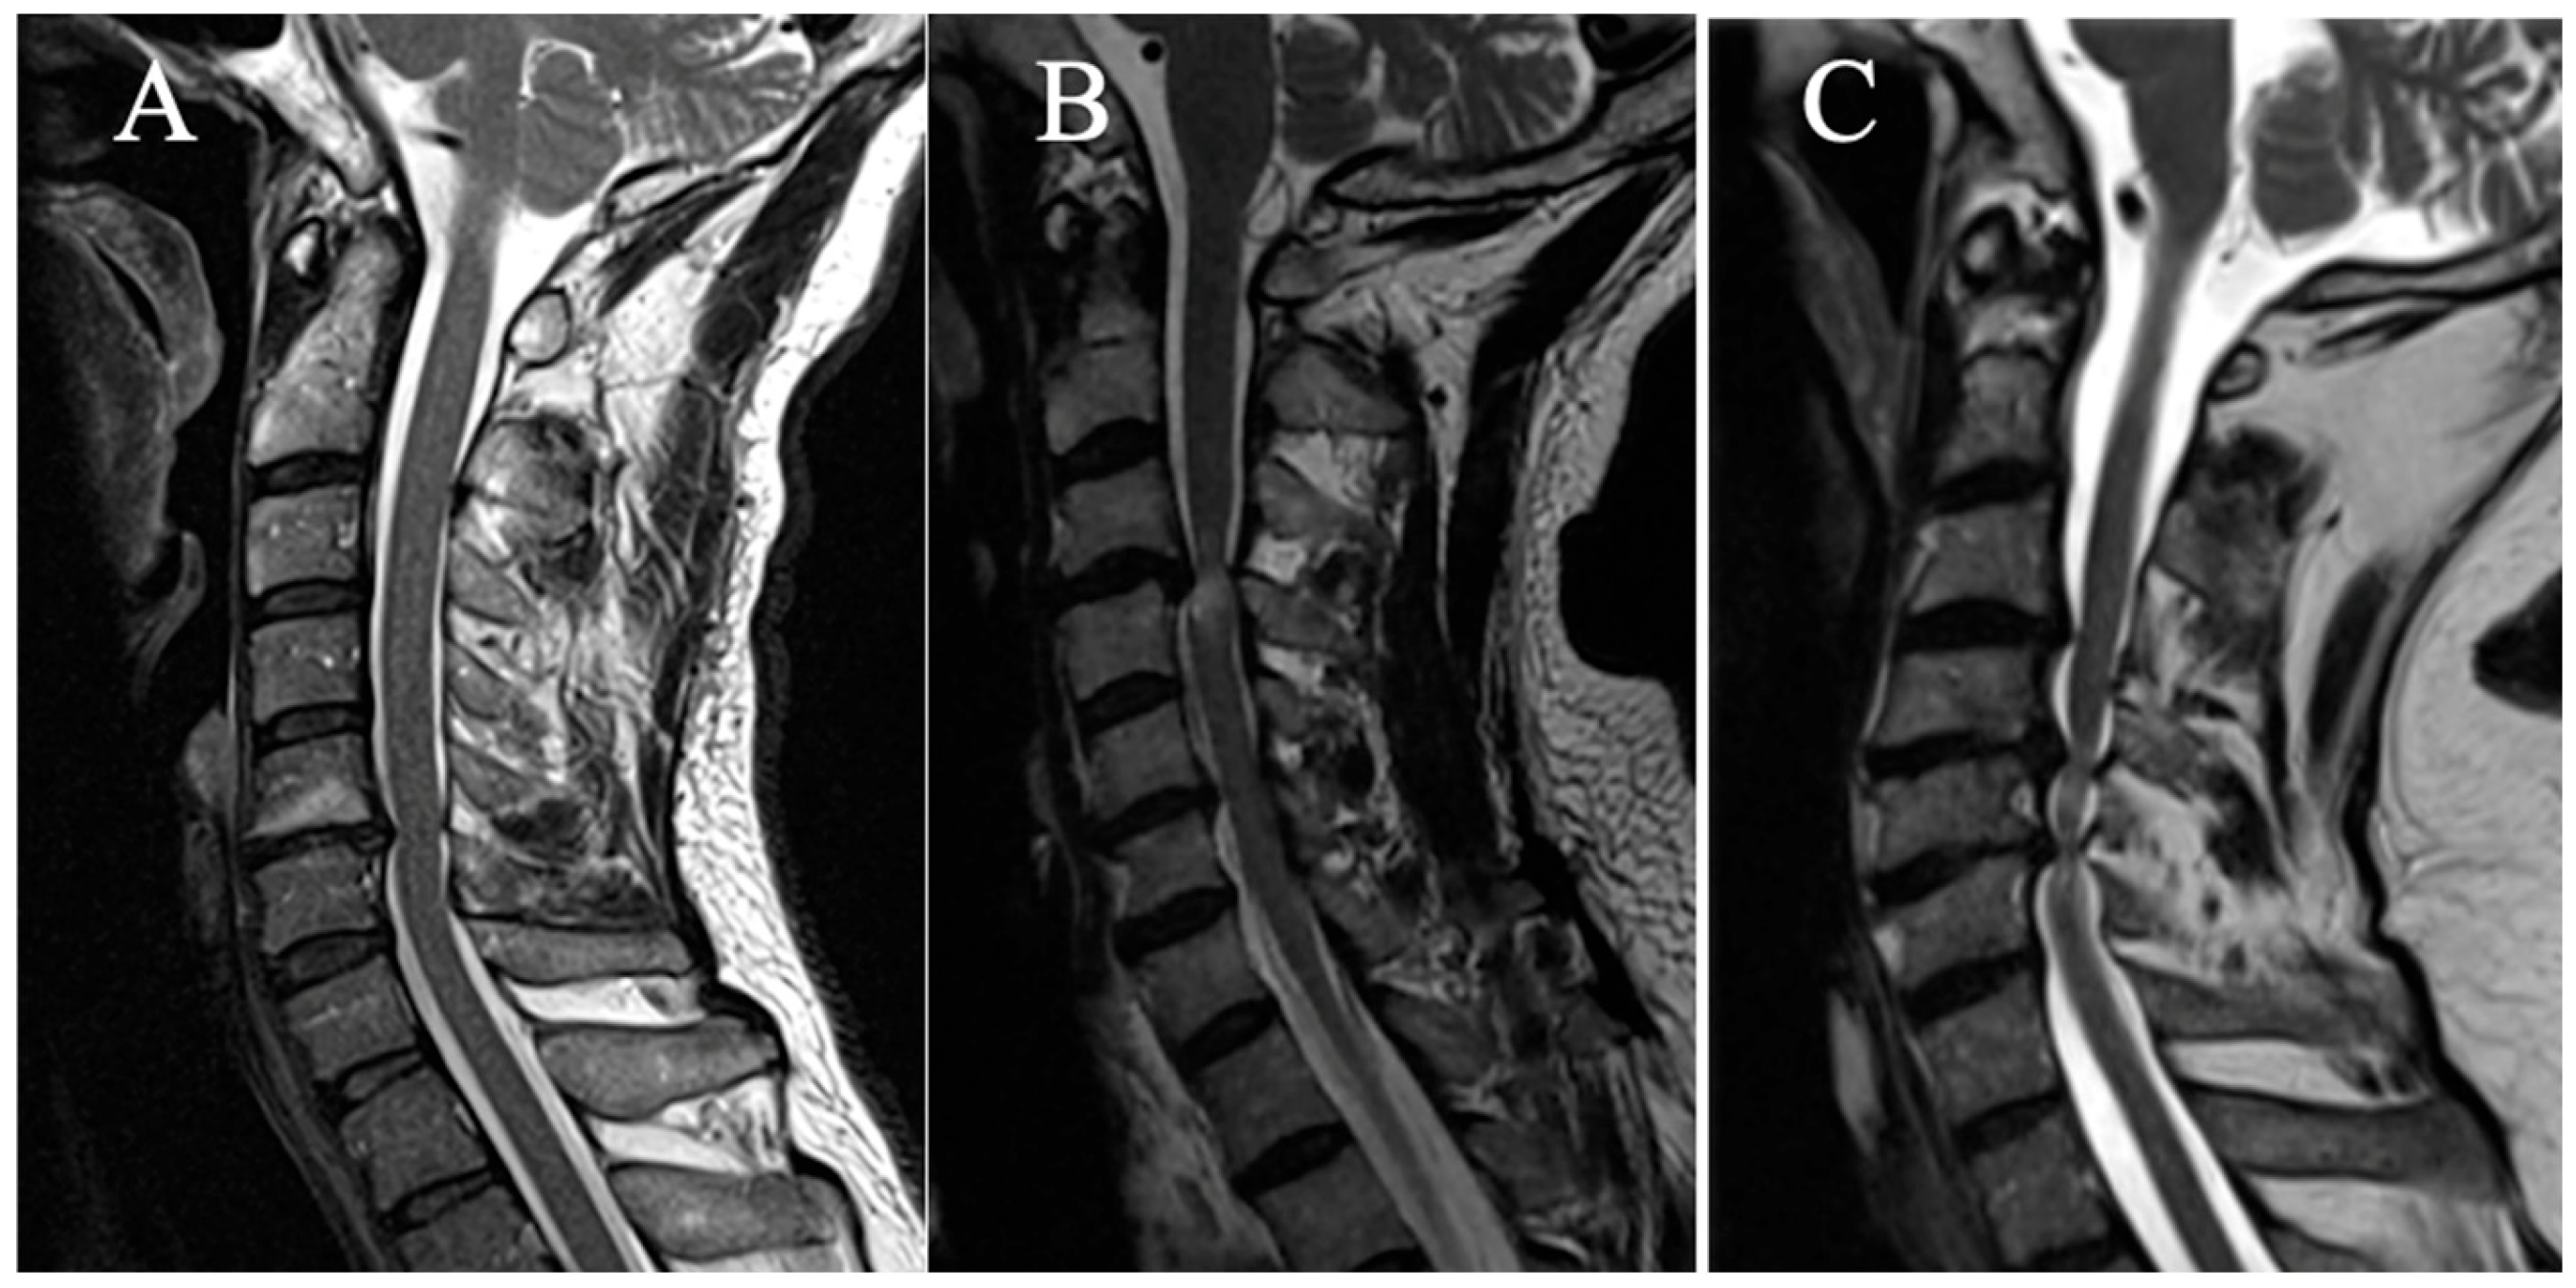

2.3.5. Local Kyphosis

Two grades were selected (based on the focal angle measured on sagittal T2-weighted MRI sequences at the level of maximum compression) (Figure 5):

(A) Lordosis or LK <4°

(B) LK ≥ 4°

Figure 5. Example of measurement of the local angle. (A) LK = 2.2°; (B) LK = 6.A°.